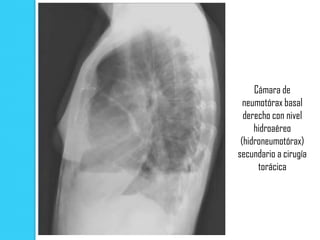

Cámara de

neumotórax basal

derecho con nivel

hidroaéreo

(hidroneumotórax)

secundario a cirugía

torácica

Cámara de neumotórax basal derecho con nivel hidroaéreo (hidroneumotórax) secundario a cirugía torácica